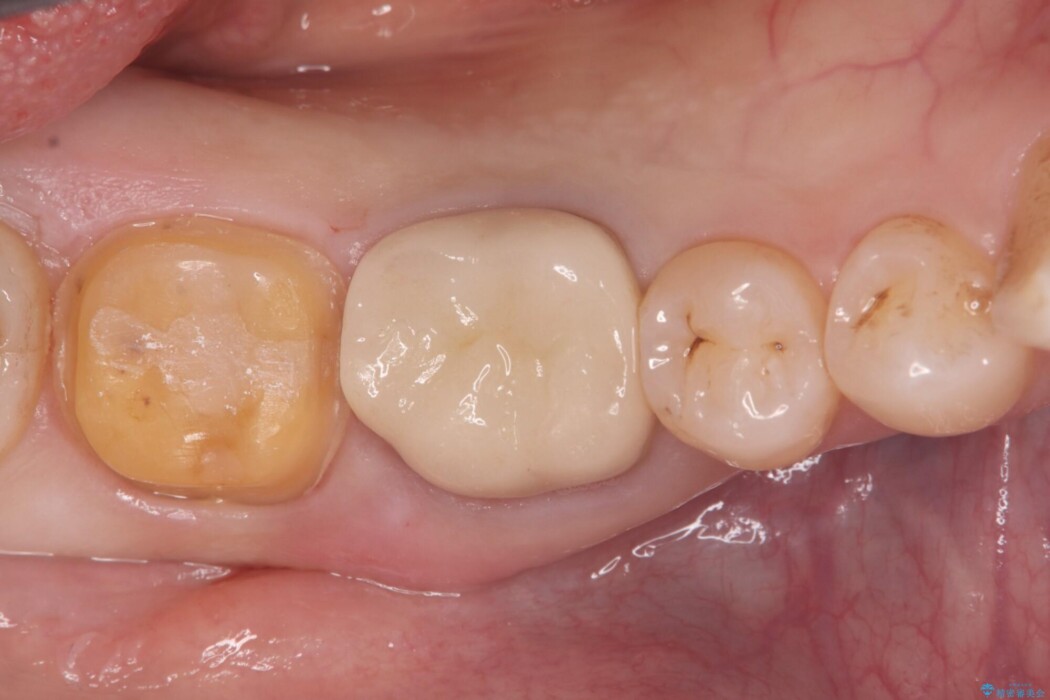

診査の結果、古い銀歯の隙間から新しい虫歯が広がっていました。ここは噛む力が強くかかる場所のため、このまま詰め物で治すと、部分的な詰め物では残存している自分の歯に負担が集中し、将来的に歯が割れてしまう「歯冠破折」のリスクが高い状態でした。

虫歯を丁寧に除去し、審美性・耐久性に優れたセラミッククラウンにやり替える治療計画を立案しました。